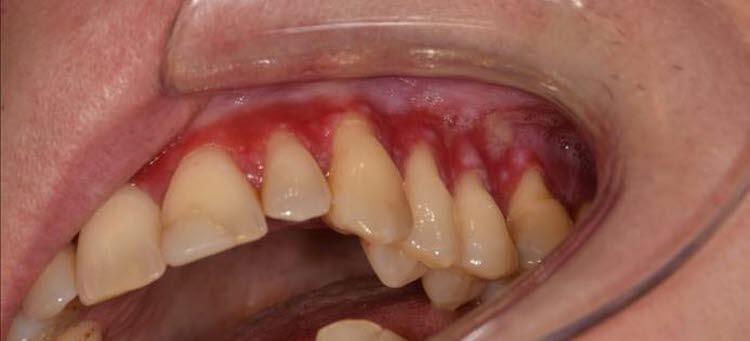

Ny forskning vid Göteborgs universitet visar att vitt snus leder till smärtsamma inflammationer i munnen som kan ta månader eller år att läka. Vilket är mycket värre skador än vad det bruna snuset leder till.

- Inom tandvården är vi väldigt oroliga för dessa skador som det vita snuset ger. Vävnadsprover visar på allvarlig inflammation, med rodnad, uttunnad slemhinna, till och med ibland sår. Det är tragiskt att våra barn och ungdomar ska behöva vara försökskaniner åt tobaksindustrin, i väntan på konkreta forskningsbevis, säger Johanna Reuterving Smajic, som jobbar med Tobaksfri utmaning på Folktandvårdens folkhälsoklinik.